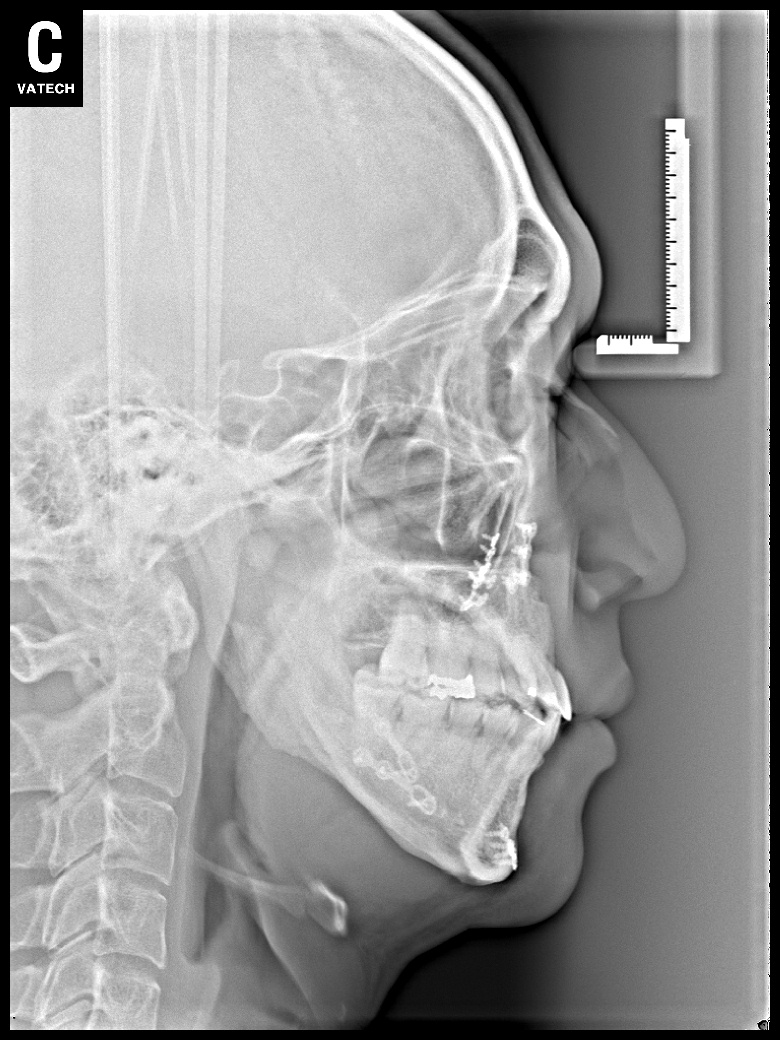

치료 전 사진입니다.